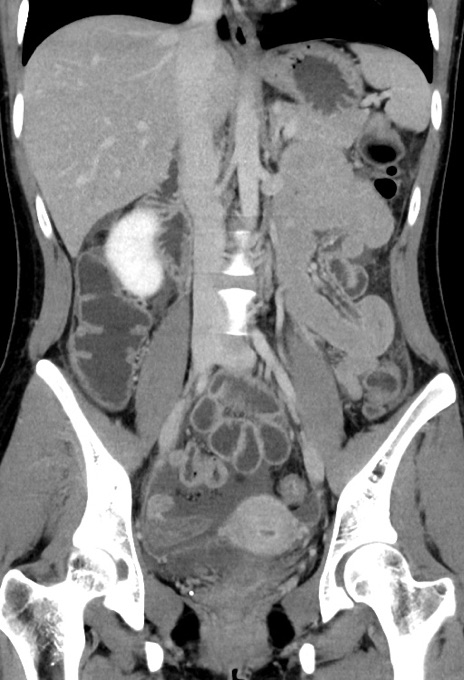

症例17(冠状断像)

【症例】20歳代女性

【主訴】嘔吐、下腹部痛

【現病歴】昨日夕食後に嘔吐し下腹部痛が出現。本日になっても嘔吐持続し改善しないため来院。

【身体所見】意識清明、BT 37.2℃、BP 108/67mmHg、腹部:平坦、やや硬、下腹部正中から右にかけて圧痛あり、反跳痛軽度あり、tapping pain(+)。

【データ】WBC 13600、CRP 14.94